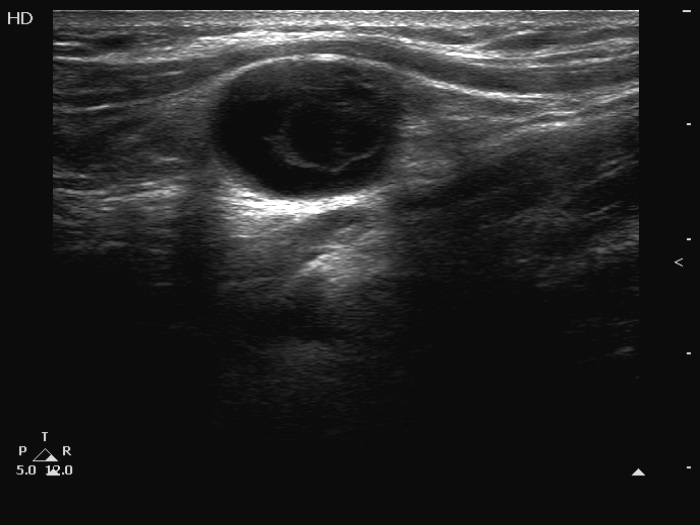

Ultrasonography. The thyroid was echonormal. The right lobe had small insignificant lesions. There were multiple nodules in the left lobe. The nodules were of different echogenicities. They included cystic lesion and a nodule with irregular borders. In some parts, the lesion showed bulging and the borders between the sternocleidomastoid muscle and the thyroid nodule were indeterminate. The palpable mass in the left submandibular area was a dominantly cystic lesion which had moderately hypoechoic solid part.

Cytology was performed form the nodular area in the left lobe and from the left submandibular mass. Total of six samples were taken. In neither case could cytology be assessed, there were only macrophages and blood elements on the smears.

Wash-out thyroglobulin of the left submandibular area resulted in 1047 microgram/L.

Final combined cytological-ultrasound-clinical diagnosis suspicion of papillary cancer metastasizing to the neck.